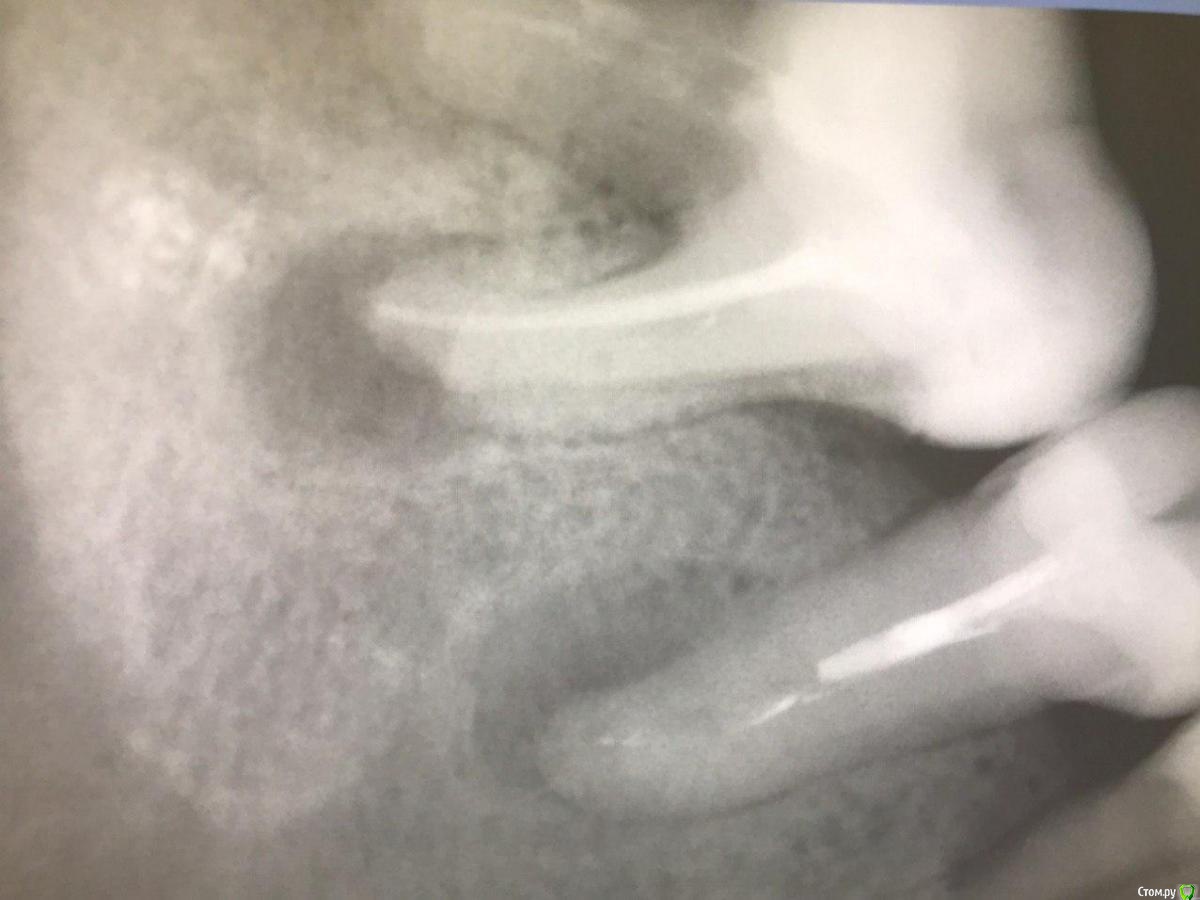

1586Doc Опубликовано 17 января, 2021 Автор Поделиться Опубликовано 17 января, 2021 первые 3 фото, ретрит 14 зуб4.5 фото 45 зуб. 4 Ссылка на комментарий